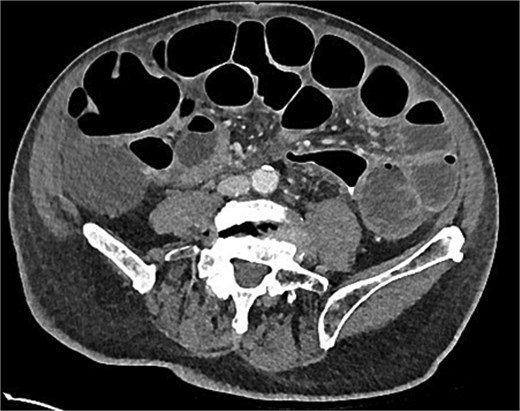

Post-operatively, recovery was slow with persistent nausea and vomiting at Day 7. A computed tomography (CT) of the abdomen with rectal contrast was ordered. This demonstrated a 6 cm thickened length of colon with rectal contrast going beyond the area of thickening and no extravisceral contrast (Fig. 1). Extracolonic findings were consistent with an ongoing postoperative ileus, with small-volume ascites and no pneumoperitoneum. The sigmoid thickening was attributed to an inflamed, healing anastomosis. Total parenteral nutrition (TPN) was commenced, and a nasogastric tube placed on free drainage to allow resolution of the ileus and anastomotic inflammation before resuming enteral nutrition.

Day 7 CT scan demonstrating features consistent with ileus with no pneumoperitoneum and rectal contrast proximal to anastomosis without contrast extravasation.